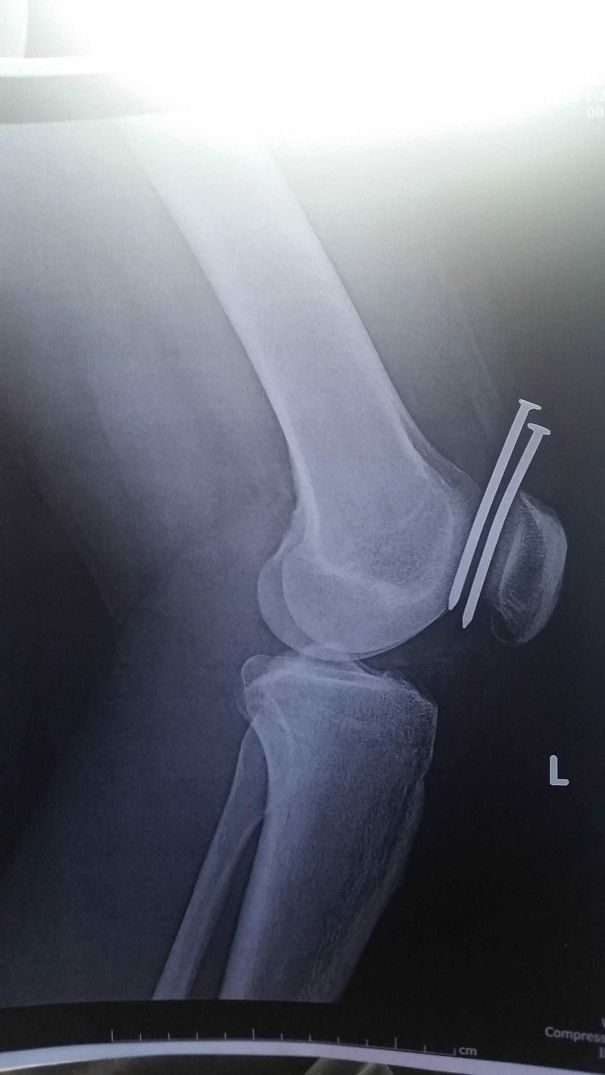

Jelas sakit sih, cuma masih disayang Tuhan banget karena nancepnya persis di tengah-tengah, nggak sampai ke tulang.